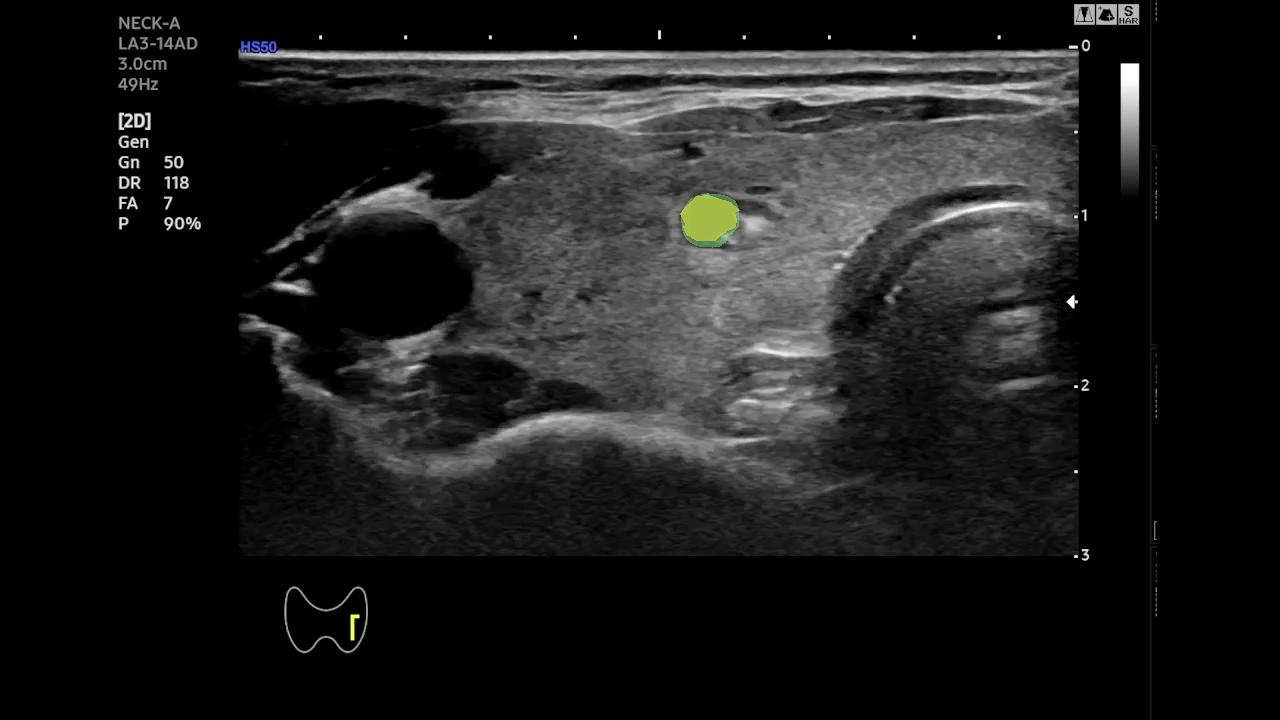

Qualitative Analysis of Temporal Stability- To better highlight the temporal behavior of SAM-2 and EMA-SAM, we visualize predictions at representative frames sampled from a complete RFA sequence. Figure 2 shows a three-row comparison: the first row displays the original ultrasound frames at selected timestamps (with ellipses indicating omitted intermediate frames), the second row shows SAM-2 predictions, and the third row presents EMA-SAM results. As the sequence progresses, SAM-2 occasionally loses the PTMC region when it becomes indistinct or is occluded by RFA bubbles, sometimes mis-segmenting nearby tissue. In contrast, EMA-SAM maintains a coherent segmentation trajectory throughout the sequence. Its confidence-weighted exponential-moving-average pointer preserves a robust latent prototype of the lesion, allowing rapid re-identification and boundary recovery once the PTMC reappears.